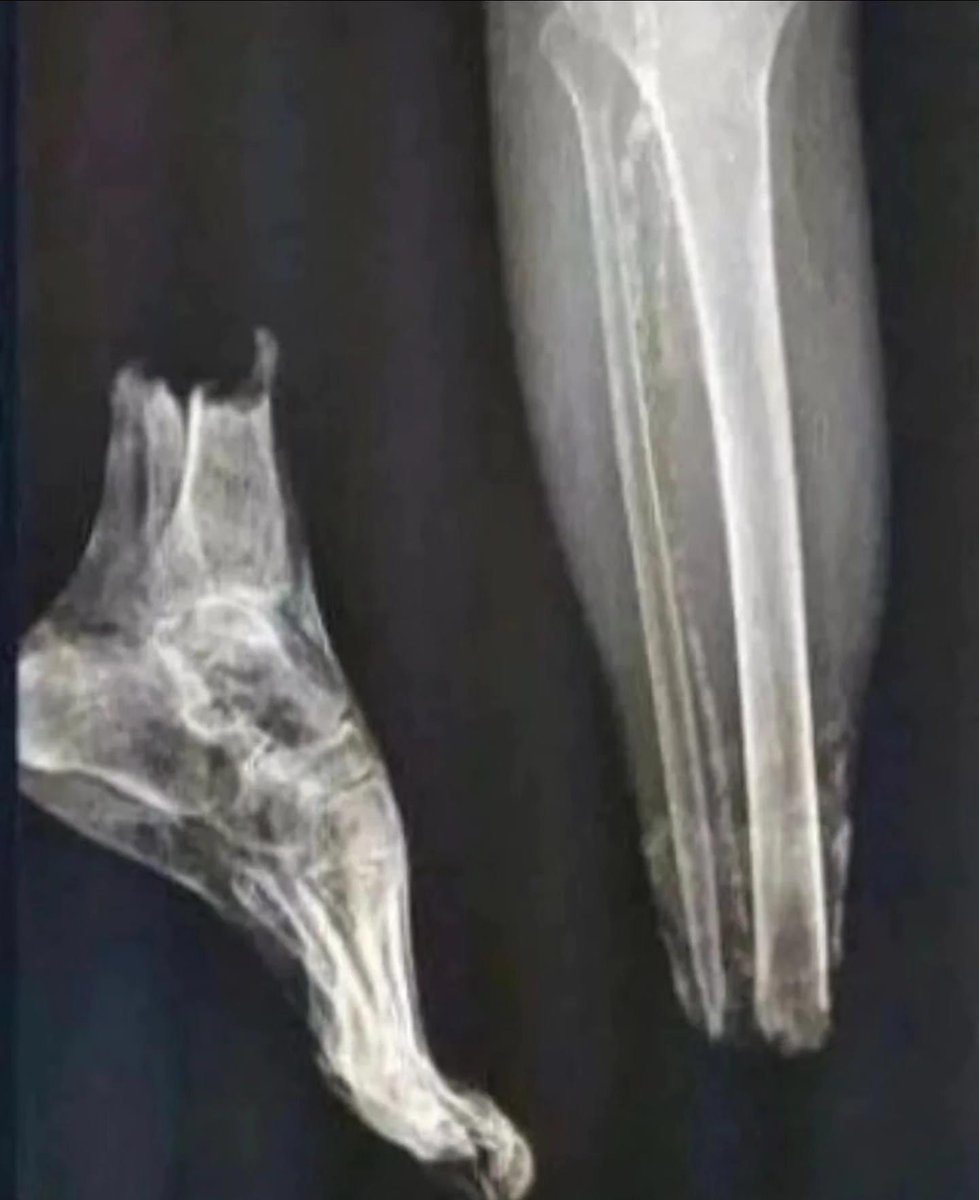

Loud Outside@LoudOutside·

You’re a doctor and you receive this case. What’s your diagnosis?